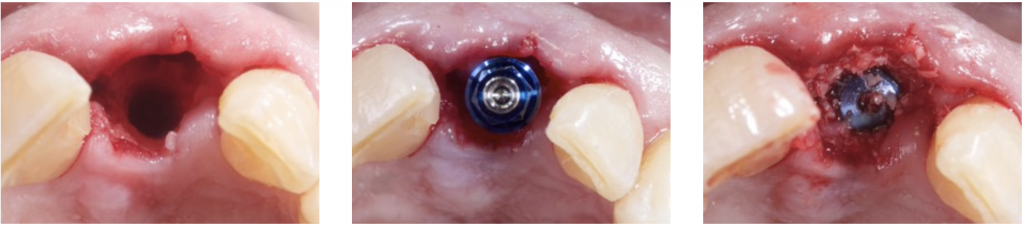

2) INTRA- ALVEOLAR DEFECT: CLASS I

This typically happens when an immediate implant is placed.

A gap will remain between the socket and the implant. Some authors claimed that if this gap is inferior to 1,5 mm, it does not necessarily need to be filled (Pauloantonio 2001).

However, Araujo and Lindhe stated that this gap should always be filled to maintain the peri-implant contour (Araujo 2011).

3) DEHISCENCE- TYPE DEFECT: CLASS 2

It is characterized by dehiscence in which the adjacent bone walls provide the volume of the area to be augmented.

Dehiscence of the buccal wall during the implant placement is the most frequent complication.